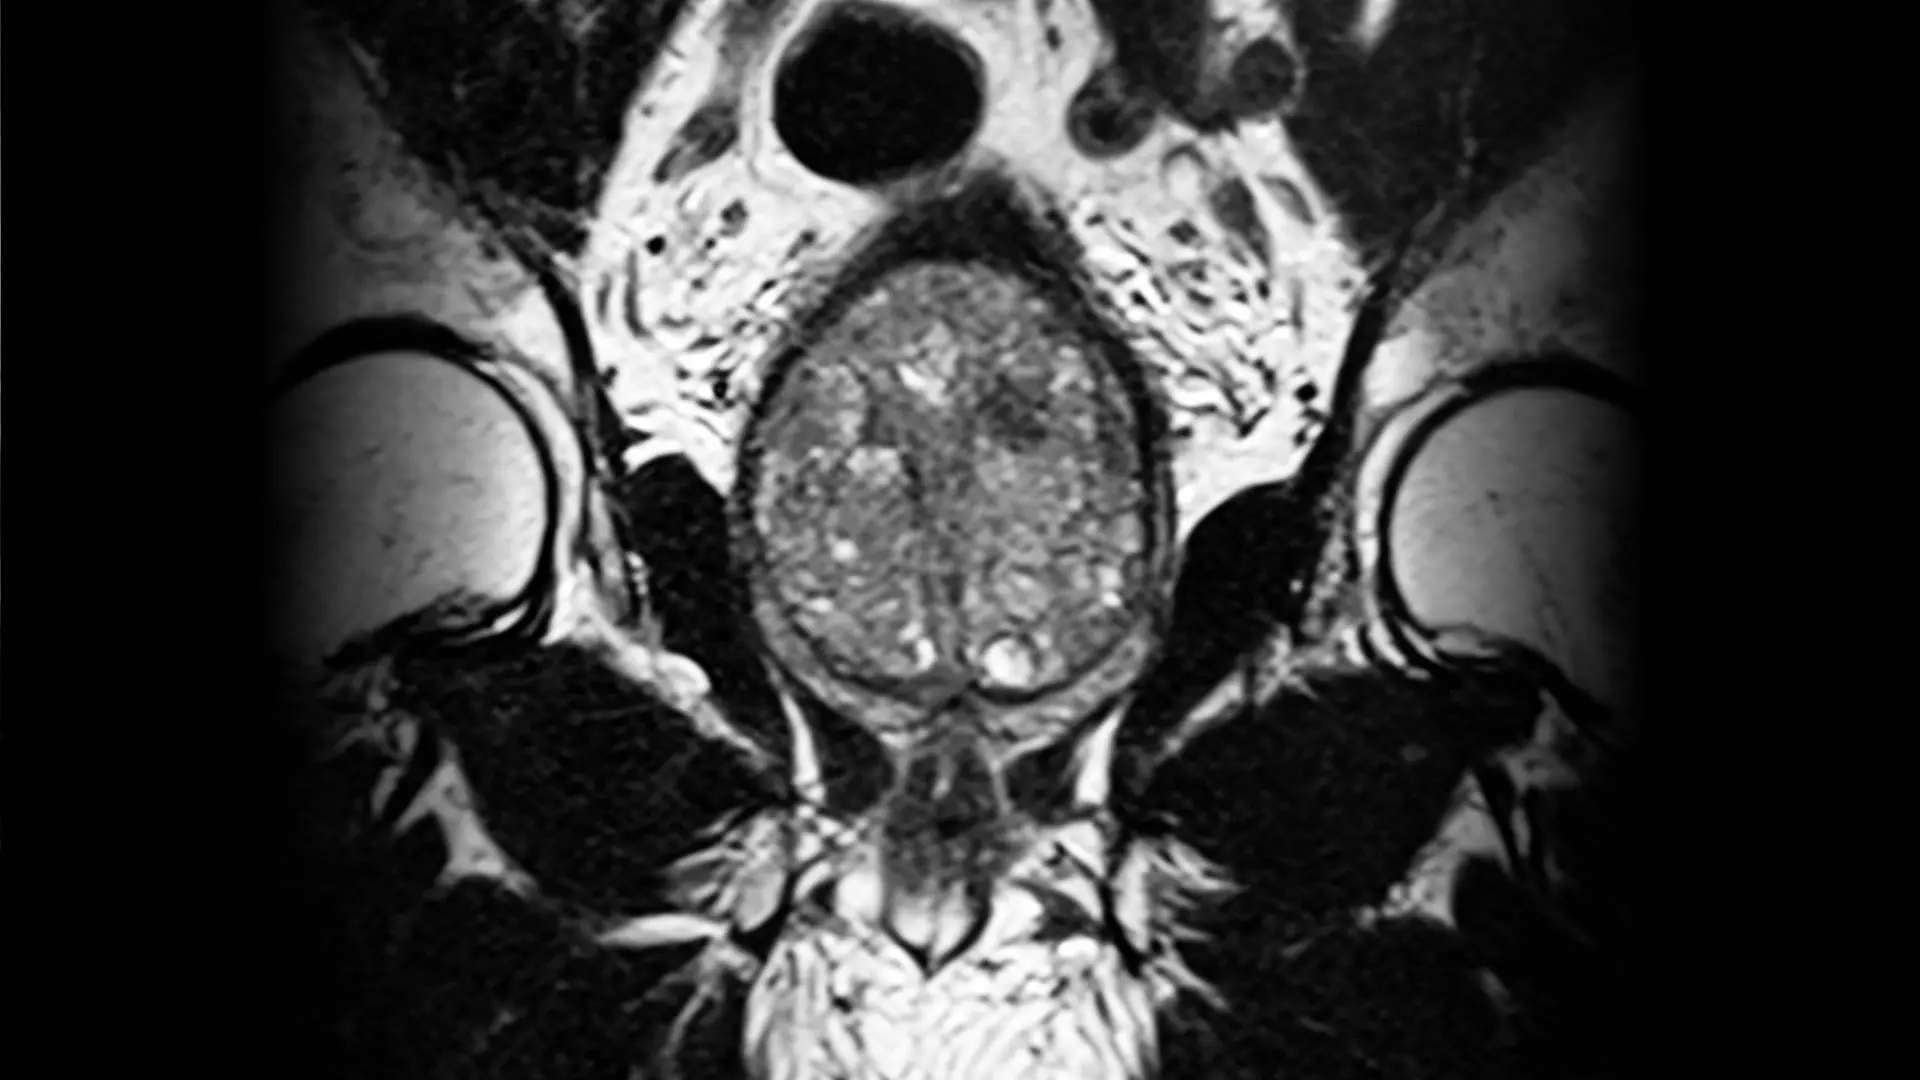

Patients undergoing surgical treatment for BPH are also benefiting from Mount Sinai’s investments in new technology, specifically the HYDROS Robotic system. This artificial intelligence-powered Aquablation platform enables greater customization of the procedure for each patient, with the added benefit of chip-on-tip imaging technology that delivers higher resolution ultrasound imaging than fiber optic technology. It also features more disposable components, which eliminates the need for re-sterilization.

“Mount Sinai played a key role in the development and refinement of Aquablation, and we were one of the first centers in New York City to introduce this new robotic system,” says Dr. Te. “With the upgrades, it is faster for us to plan and perform the procedure, not to mention safer for our patients because we are able to do all that using artificial intelligence.”